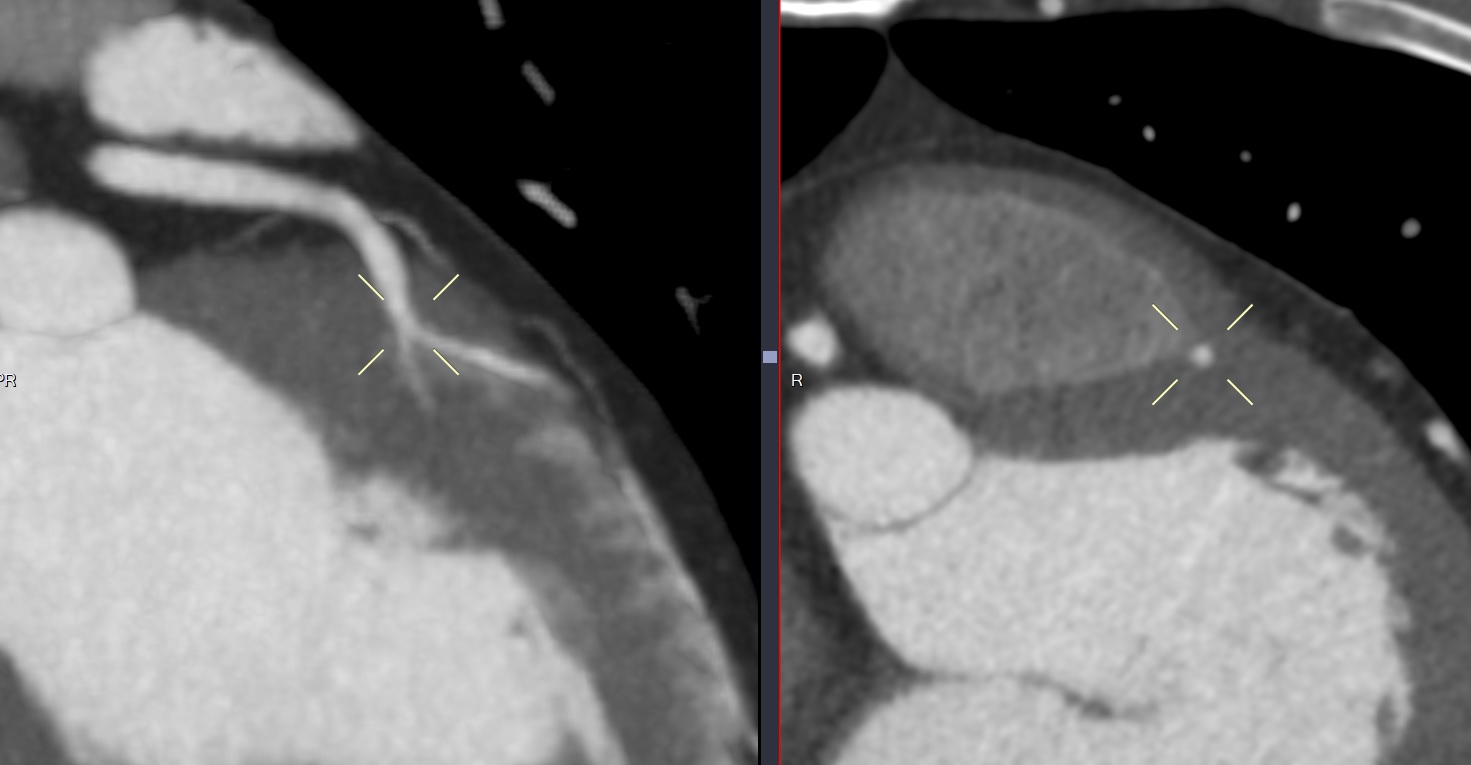

Pont Myocardiue court

Pont myocardique profond